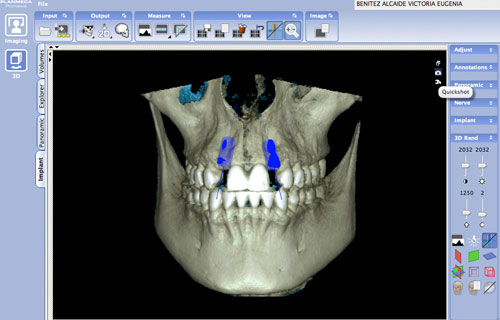

En la panorámica se observa la presencia de ambos 3º molares superiores y la agenesia de los inferiores así como de los laterales motivo de la consulta , y en la rx simple en proyección dorso palmar de su mano, observamos el cierre de todas las fisis o cartílagos de crecimiento, lo que indica una maduración esquelética completa.

Decidimos entonces tomar una nueva panorámica y realizar un Índice de Scarpa para corroborar su edad ósea.

Ante el estudio de scanner de haz de cono, la situación ósea es normal, de un hueso densidad tipo 4 (entre 155 y 237 UH a distintos niveles del hueso remanente) de un ancho vestíbulo palatino e inciso apical adecuado, pero inter dentario escaso.